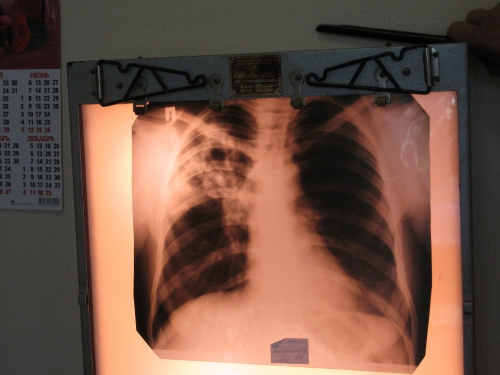

Не коронавирусом единым - как в Мелитополе лечат от туберкулеза

Судьба Мелитопольского противотуберкулезного диспансера повисла в воздухе. По городу пошли слухи, что его закроют, как и десятки других на территории Украины, а все больные пойдут к семейным врачам и понесут болезнь в массы.

И действительно, предпосылки к тому, что стационар закроют, есть. Стационар, а не всю службу целиком. 1 апреля стартует второй этап медреформы, и предполагается, что финансирование фтизиатрической службы будет несколько иным, по сравнению с другими учреждениями медпомощи. Так, согласно новой формуле финансирования, бюджет фтизиатрической отрасли Запорожской области на 2020 г. составит 34 млн грн, что почти в три раза меньше, чем потребность, которая была бы в 2020 г. Отсюда вывод - сеть должна быть изменена. Об этом речь шла на одном из брифингов в стенах Запорожской обладминистрации, посвященному реформированию отрасли.

Почти каждый четвертый случай туберкулеза в Украине - это мультирезистентный туберкулез (МРТБ), который не поддается лечению противотуберкулезными препаратами первой линии. И этому частично способствует неэффективная система оказания помощи в туберкулезных диспансерах. Ведь длительное пребывание в стационаре и отсутствие разделения больных с различными формами туберкулеза увеличивает риск повторного заражения и способствует распространению МРТБ.